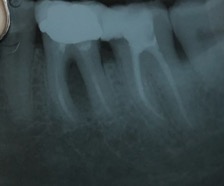

Capita spesso di incontrare denti già devitalizzati in maniera impropria che necessitano, seppur asintomatici, di essere ritrattati per evitare che i granulomi infetti visibili radiograficamente si evolvano riassorbendo tutto l’osso sottostante.

Un adeguata endondonzia serve per salvare quei denti che altrimenti sarebbero destinati ad essere estratti. Quando un dente viene devitalizzato viene privato della sua irrorazione sanguigna e del nutrimento, rendendo la sua struttura più “vetrosa” quindi più fragile e soggetta a fratture. Per questo motivo è consigliabile nella maggior parte dei casi capsulare i denti una volta che hanno perso la loro vitalità.